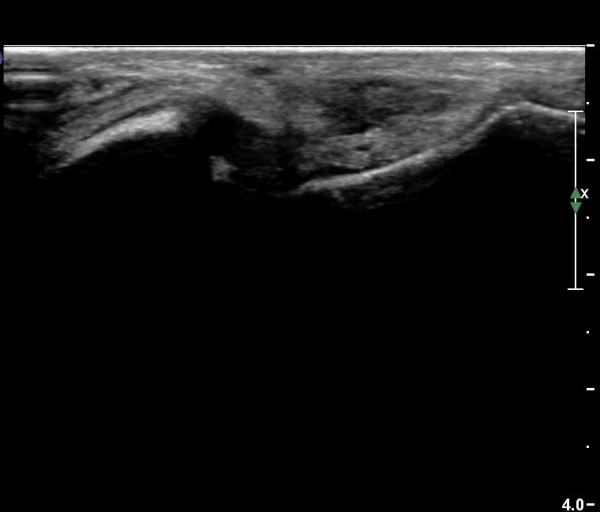

¹ß¸ñ°üÀý ¾ÕÂÊ Á¾´Ü¸é°Ë»ç¿¡¼­ ƯÀÌ ¼Ò°ßÀ» º¸ÀÌÁö ¾ÊÀ¸³ª(»çÁø 1)